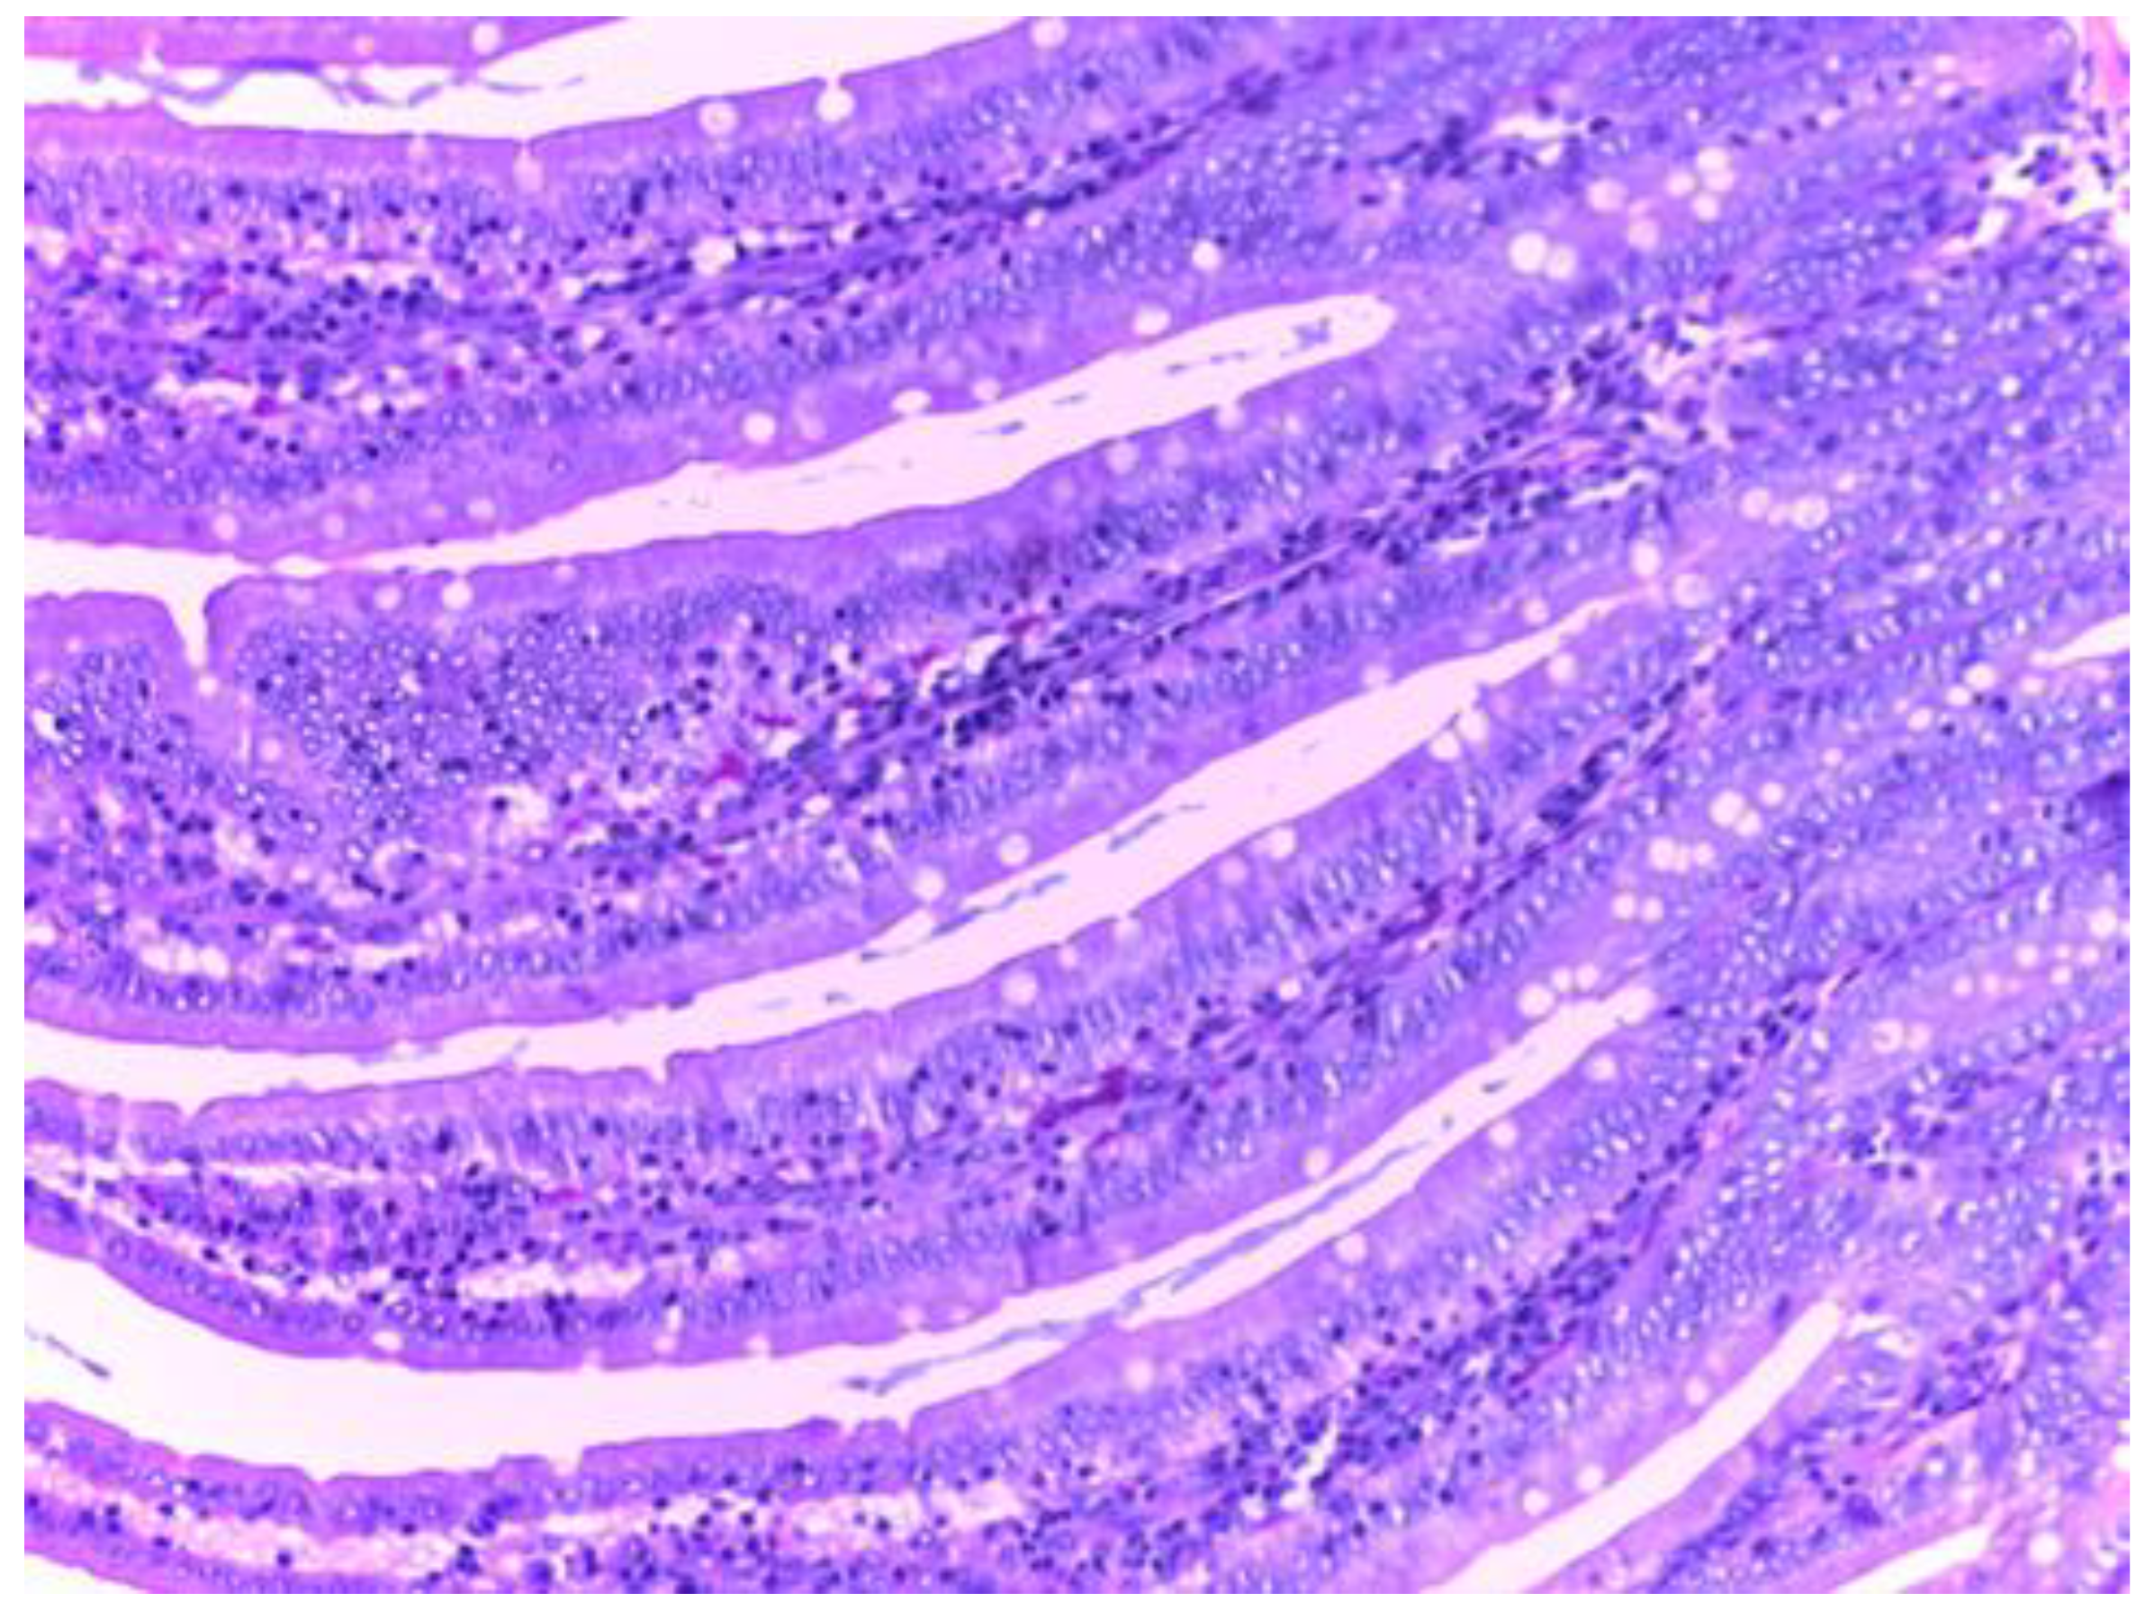

Histological examination of the small intestine in animals treated with diclofenac (group II) revealed an abundant inflammatory infiltrate, even with small lymphoid follicles and few neutrophils in the lamina propria. No mucosal erosions are observed, and the submucosa, tunica muscularis and serosa have a normal histological appearance (Figure 10).

The histopathological results support the obtained biochemical results. The analysis of the intestine tissue sections showed that in the animals treated only with diclofenac, there is an abundant inflammatory infiltrate with the presence of neutrophils in the chorion structure of the intestinal mucosa. However, no mucosal erosions were observed, and the underlying structures retained their normal appearance. This may be due to either the inadequate duration of NSAID exposure or the low dose used, although these were consistent with those used in the literature.

Figure 10. Histological appearance of the small intestine in animals in group II (H&E stain, 20X).